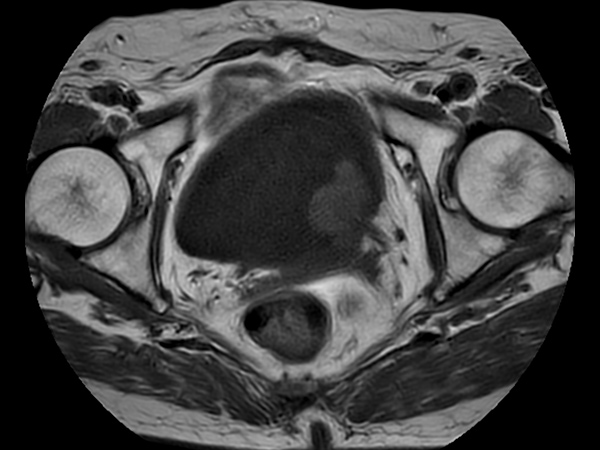

T2w TSE MultiVane XD